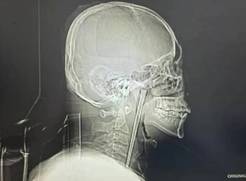

【单机】男子误吞12厘米筷子忍了8年才取出 网友:是个狠人

近日,辽宁大连46岁的王先生因咽部突发剧烈疼痛、异物感难忍,前往大连理工大学附属中心医院耳鼻咽喉头颈外科就诊,一项检查结果让医护人员大吃一惊——一根长达12厘米的金属筷子,竟在他的咽部“潜伏”了整整8年之久。有网友留言感叹“真是个狠人,竟然能忍8年”。